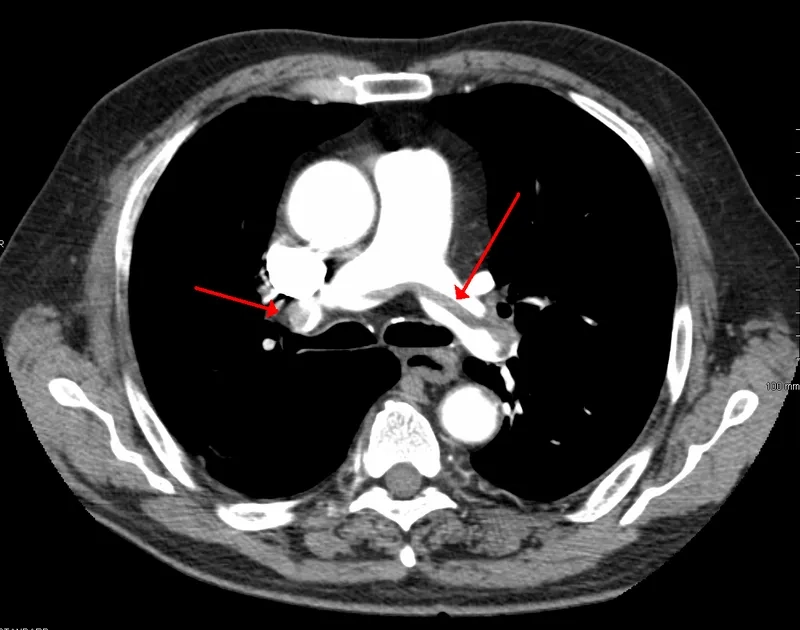

A CT scan for a definitive pulmonary embolism diagnosis

The PE survival rate is high with prompt diagnosis and treatment. If you experience any symptoms, seek emergency medical care immediately. A swift response is crucial for managing the condition and planning your life after pulmonary embolism.